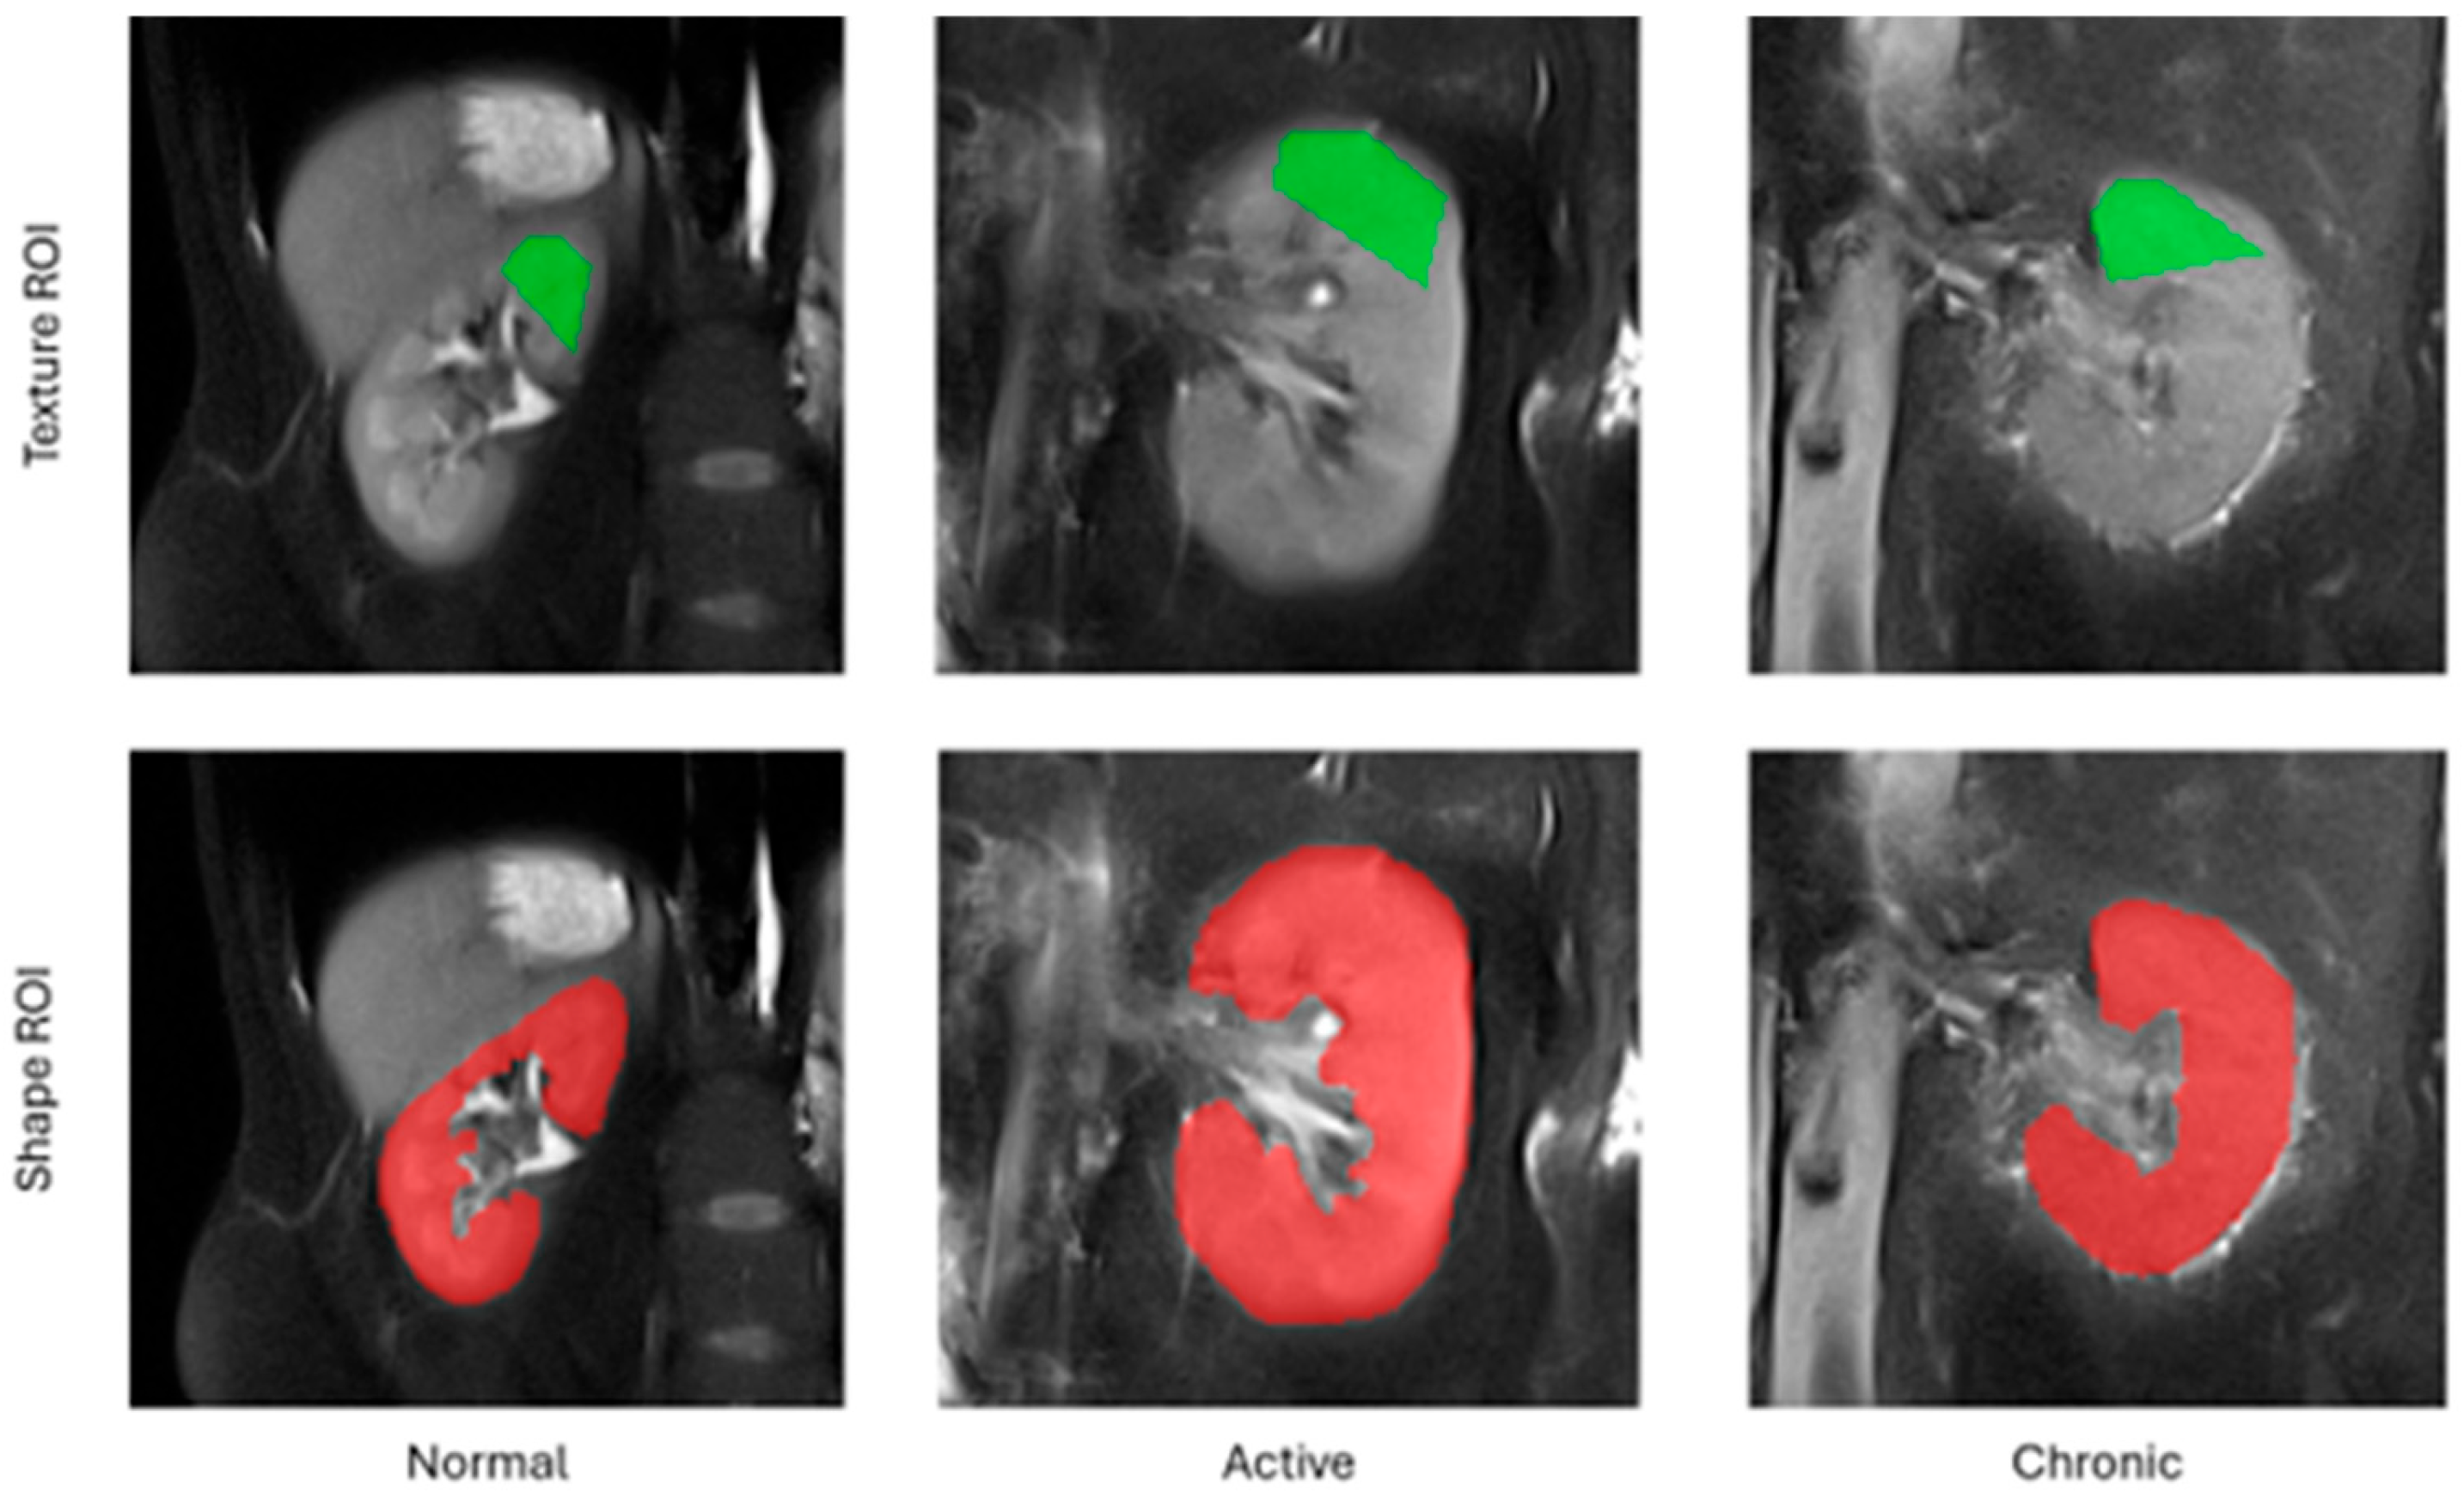

The employed feature extraction workflow comprised the following steps. For each subject included in this study, a middle cross-section of the kidney along the anterior–posterior acquisition axis was selected from the entire 3D volume. Following this, a pentagonal region of interest (ROI) was manually drawn over the tissue area directly above the kidney pelvis (Figure 1). This region was selected for analysis because it is anatomically most representative of the kidney and most repetitively observed on MRI images. A pentagonal ROI was chosen because it was the simplest yet sufficiently flexible shape that could be adjusted to the geometry of a kidney. Next, the pixel intensities within the ROI were normalized to the range defined by the mean intensity of the ROI and the interval of ±3 standard deviations (so-called 3-sigma normalization). The normalization ensures that the computed features are independent from any acquisition settings, scanner parameters or signal energies which may differ between readings, i.e., all factors which affect final image brightness and contrast. Finally, the texture analysis was performed within each ROI, and the computed feature vectors completed with a category label (1—normal, 2—active, 3—chronic) were stored in an output CSV file.

Figure 1.

Example regions of interest for texture and shape analysis.

In addition to texture analysis, a series of geometrical attributes were identified based on the entire selected 2D cross-section of the kidney chosen for texture analysis (TA). The set of morphological parameters consisted of 97 features which described kidney shape, such as area, circularity, convexity, principal orientation, contour–skeleton attributes, second-order moments of inertia, or perimeter profile attributes. This group of descriptors was included in the analysis for two reasons: texture alone does not determine all the differences in tissue morphology regarding lesion category, and it is the kidney shape which improves the performance of the ultimate classification model. Each kidney image was represented in the final data set by only one feature vector; as such, there was no risk of data leakage while partitioning the vectors into train and test folds during the exploratory analysis.